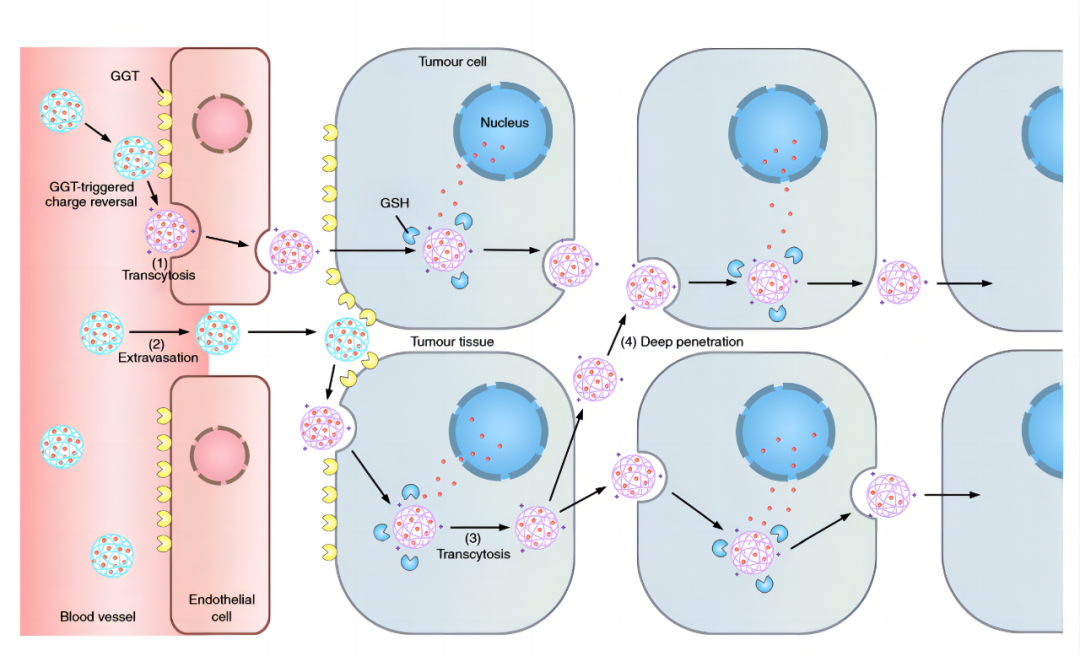

肿瘤组织内渗透性差仍然是药物递送的瓶颈所在。渗透性差是当前众多抗肿瘤药物临床失败、临床药效不佳的重要原因。普利制药与浙江大学联合创制的胰腺癌纳米创新药PLAT001,首次构建了γ-谷氨酰转肽酶(GGT)介导的电荷反转聚合物,并将其应用于抗肿瘤药物的递送,突破纳米药物在实体瘤中的渗透性瓶颈。

本项目已经获得美国FDA临床试验批件,标志着普利制药进入到生物医药、纳米科技、新材料等新领域。这是我国自主研发的首个在美国获批临床试验的纳米药物。PLAT001核心专利荣获海南省专利优秀奖。

基于该纳米药物递送平台,普利制药正在开发递送小分子抑制剂、mRNA、多肽等治疗成分的新型纳米药物。